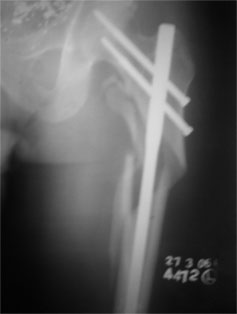

2009

Again operated for the same, this time fixed with locking plate and dynamic hip screw.